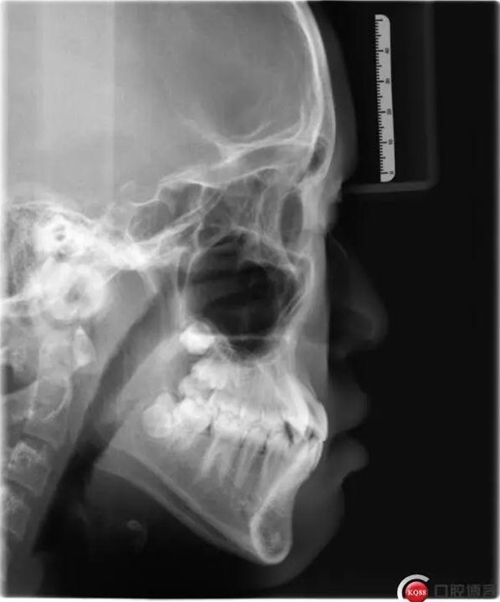

此病例主要考慮的是垂直骨面型,矢狀骨面型,前牙覆合覆蓋及尖牙關(guān)系,側(cè)貌